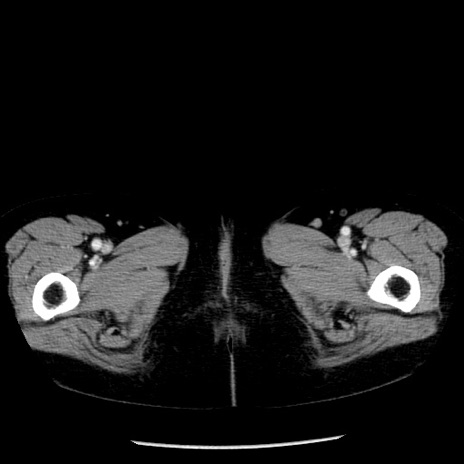

冠状断像